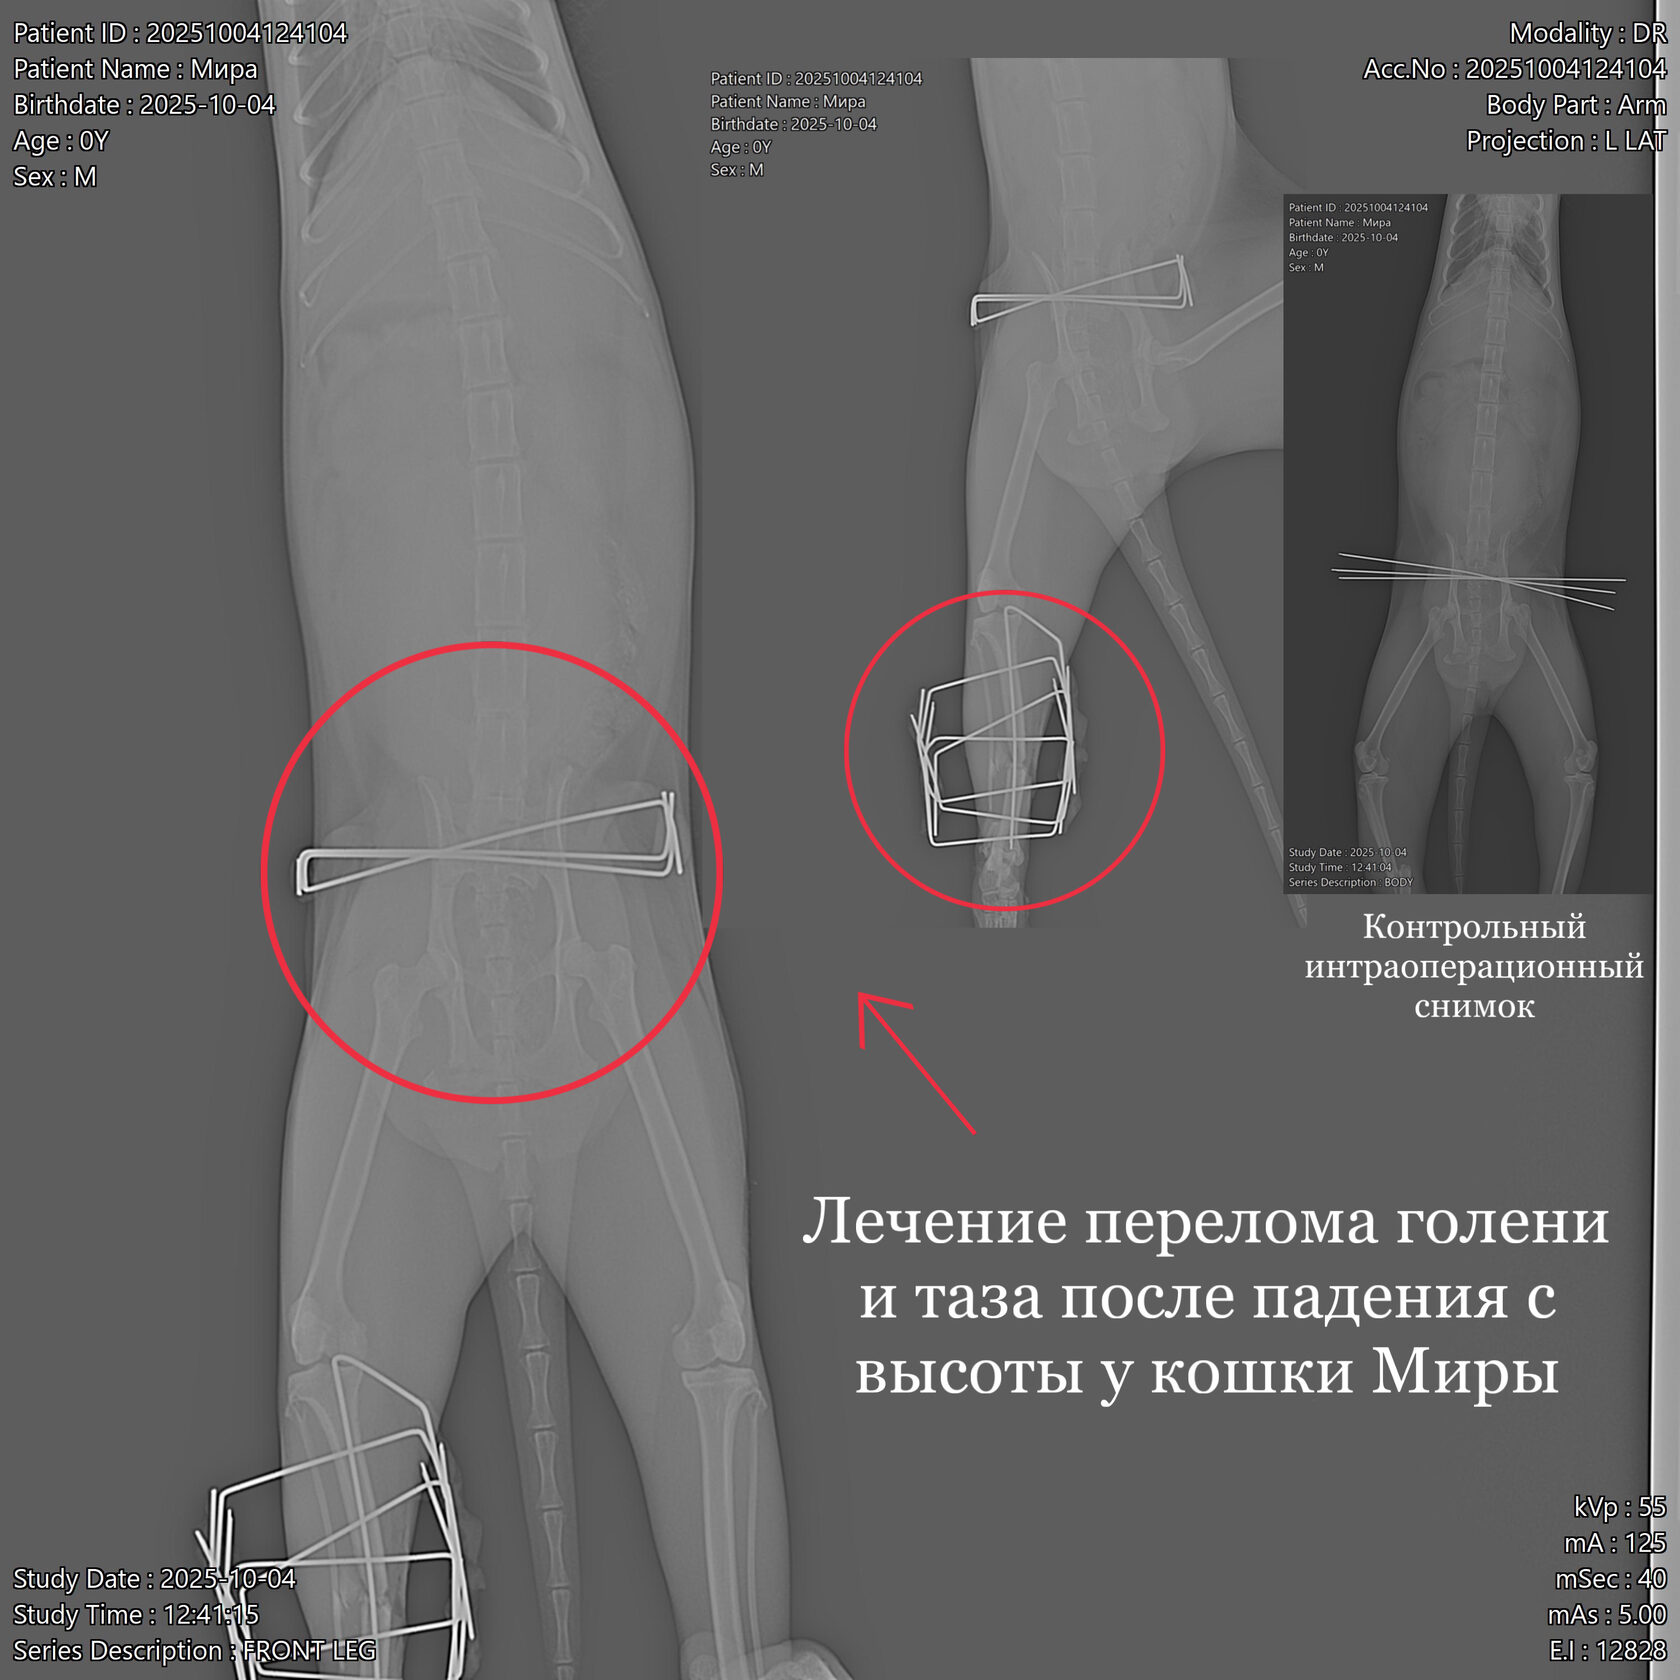

В клинику обратилась собака породы кане-корсо (2 года). Со слов владельцев животное убежало из дома на 11 дней, вернулась с висячей конечностью, в течении 3 дней владельцы искали клинику для проведения операции. По результатам рентгенологического исследования выявлен диафизарный поперечный перелом голени со смещением. По согласованию с владельцами провели металлоостеосинтез трубчатых костей накостной пластиной. В ходе операции было обнаружено образование псевдоартроза (ложного сустава), костные отломки были зачищены и репонированы (сопоставлены) согласно их анатомии. Владельцем были даны послеоперационные рекомендации по уходу за животным.